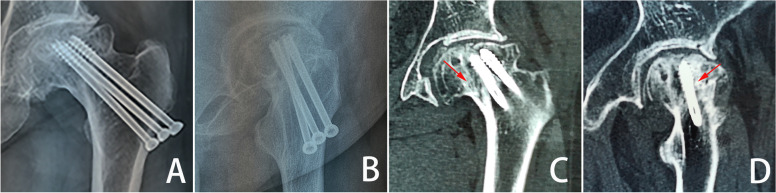

Fig. 4.

Proximal sclerotic femur model

Based on the micro-CT images (Fig. 2B), we concluded that the entire femoral neck was sclerosed. Therefore, the model of sclerosis around the screw was designed to extend the sclerotic region of the femoral neck upward in a frustum of a cone, beyond the cannulated screws and downward to the lateral femur. Meanwhile, the sclerotic bone filled the entire femoral neck (as shown in Fig. 4).